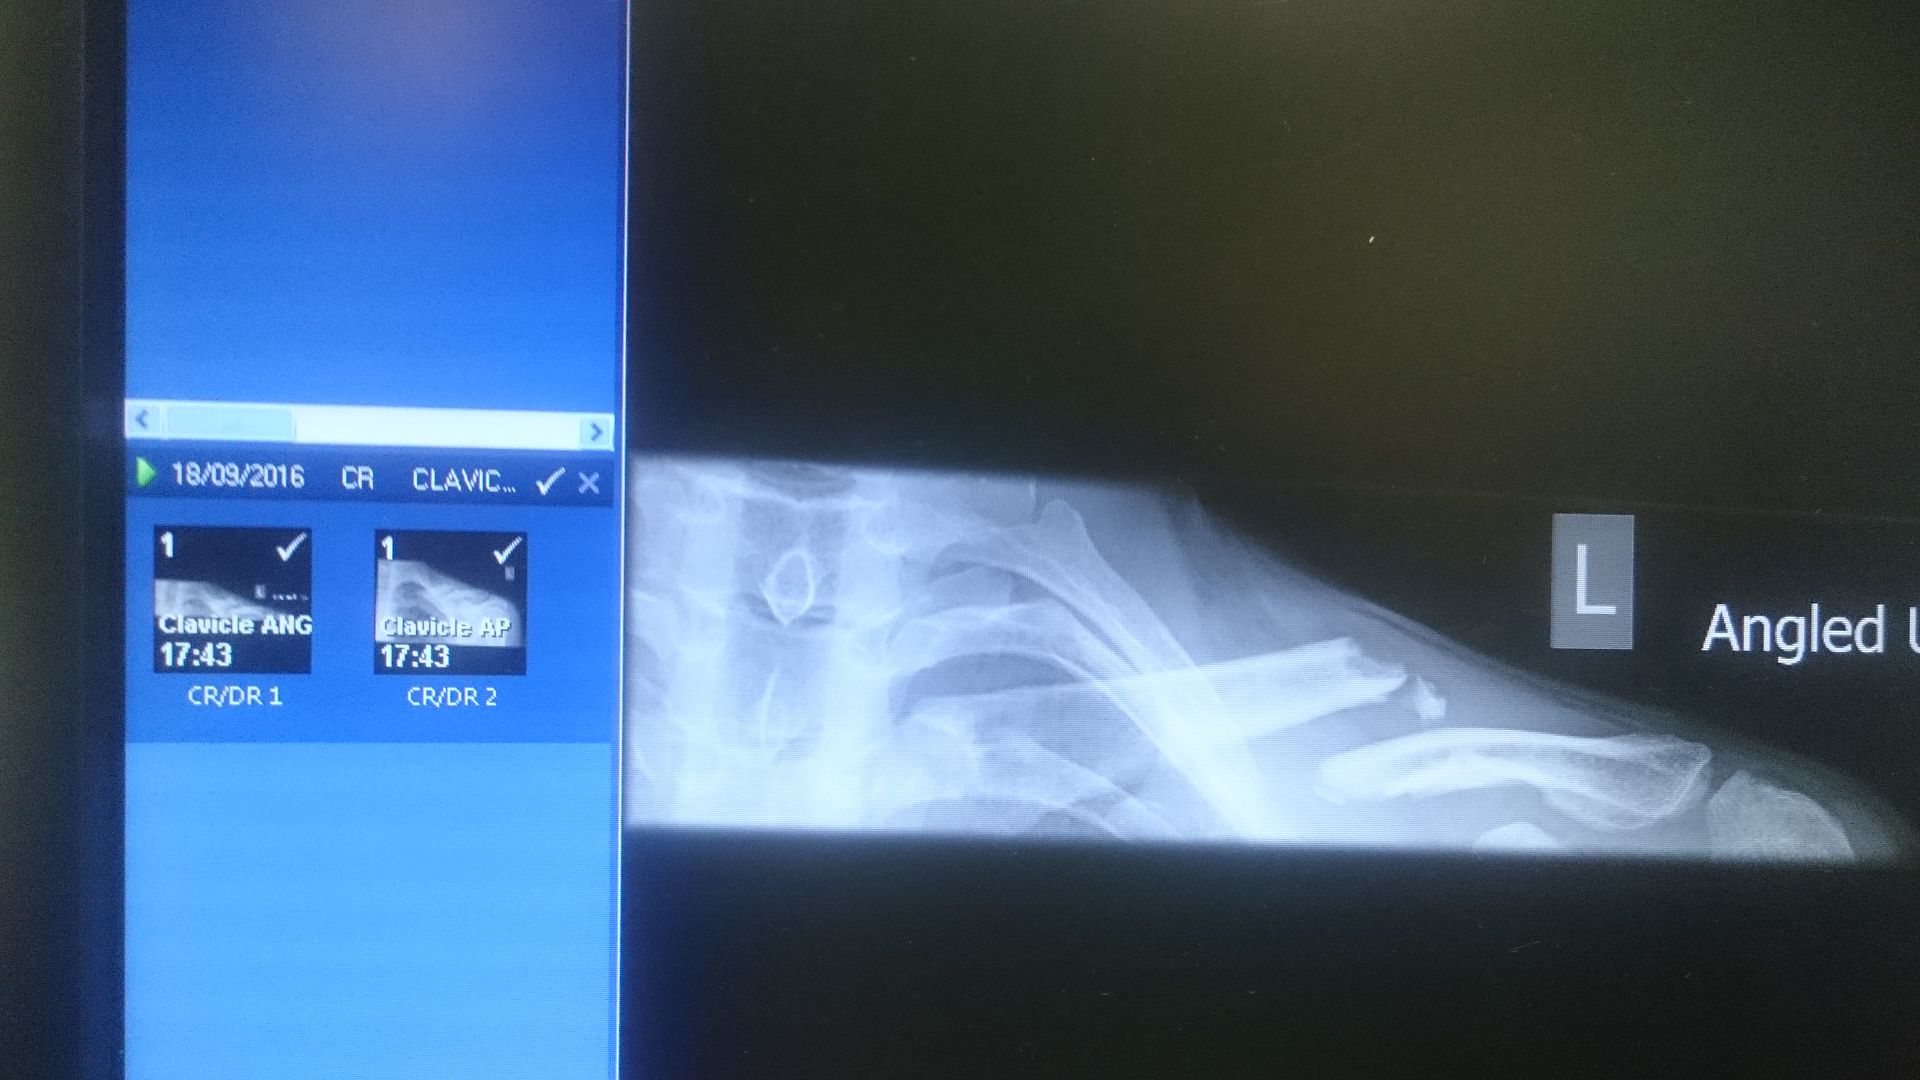

I'm not a doctor but the advice I got from other doctors is that a 4 to 5cm overlap when broken is not uncommon (similar to the xray above) and the bone will usually push itself back out reducing the overlap significantly and heal up fine if a little wonky.

I'm a GP not an orthopod so not going to comment on your X-ray, other than to say it looks similar to when I broke mine, which healed without surgery, but might have healed quicker with surgery. Of course there are risks with surgery and I might also have ended up worse off. Which is why you need to speak to the person treating you not the Internet.